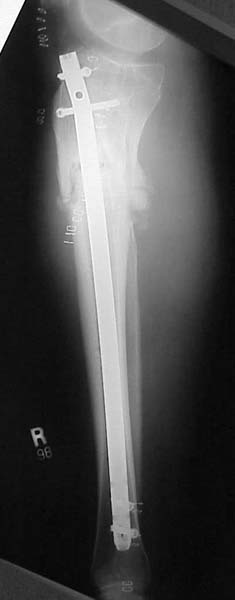

Thanks for the input on the tibia malunion w/ multiple plane deformity. I decided on a single cut osteotomy and IMN fixation based on desire to walk early, return to professor duties, and my previous experience w/ similar deformities (see another tibial malunion -below). The opening wedge was packed w/ a combination of autograft, allograft and demineralized bone.

Another tibial malunion -

Pt was 10 yrs s/p open tibia fx treated in a cast w/ IR, varus, 2 cm short, and recurvatum. He has done well post op.

18 mos postop